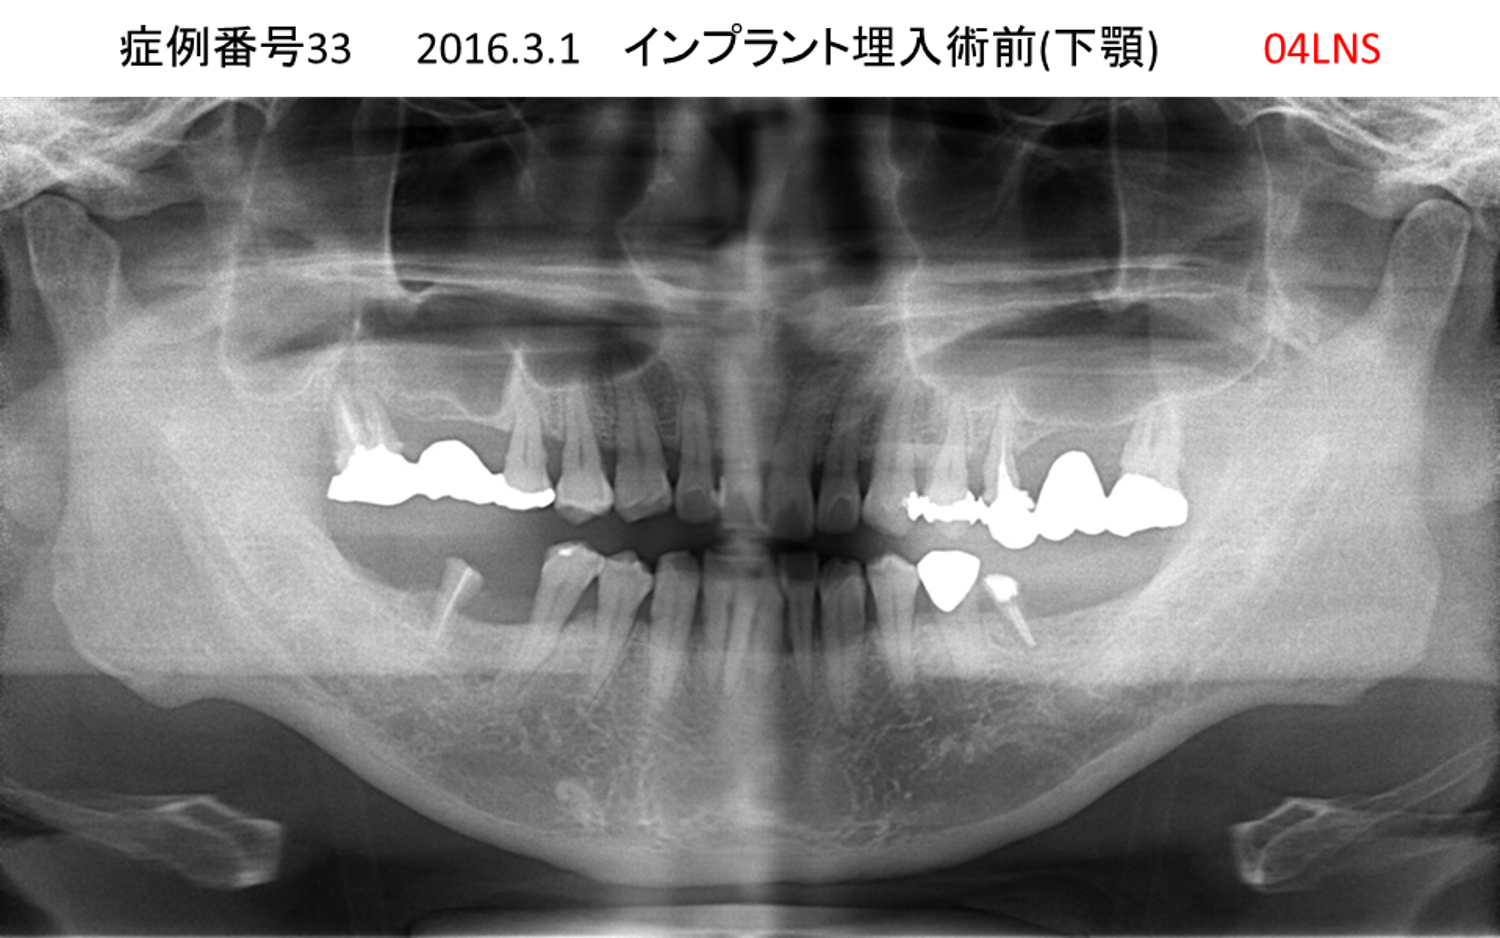

左下の奥歯が痛い患者様のインプラント症例

| 治療名称 |

インプラント |

| 治療費用 |

215万円+税 |

| 治療期間 |

5か月 |

| 患者さんの症状(主訴) |

左下の奥歯が痛い。 |

| 治療内容 |

| 治療結果 |

痛み無く、噛める。 |

| 治療の注意点(リスク/副作用) |

インプラントが壊れたら再治療が必要 |